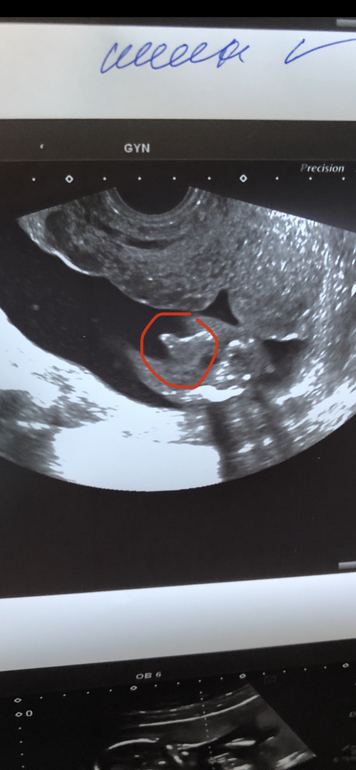

А это наш мальчик) теперь надо думать, как назовём 😐